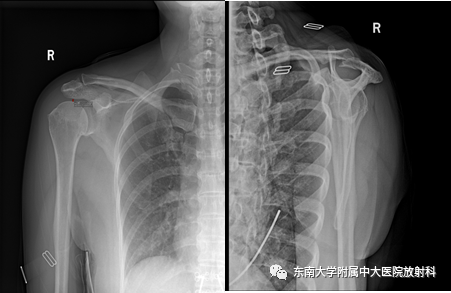

肩峰下撞击综合征影像表现